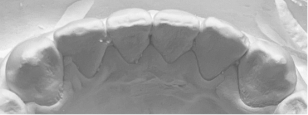

2):当院の矯正の調査法(世界的権威リトル教授の調査方法)

観察方法はPARスコアではなく、もう少しダイレクトな評価になるリトル教授らの方法を使いました。つまり右図のように、後戻りが一番現れやすいと言われている下の前歯において、歯と歯の接触点間の距離をmm単位でデジタル写真上で計測し、それらの合計のミリ数を「指数」とするものです。歯並びが綺麗であれば“0”に近い数字になり、数字が大きいと悪い歯並びを意味します。この写真の歯と歯の接触点間の距離の合計は9.3mmでしたから、指数は9.3になります。